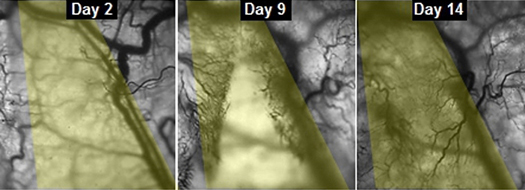

Kendini onarabilen yapay kas

Araştırmacıların açıklamasına göre, kaslar niş adı verilen noktalarda bulunan kök hücreler sayesinde kendini yeniliyor. Bu kök hücrelere “uydu hücre” adı veriliyor. Üstelik kasın kendini iyileştirici özelliği hem laboratuvarda hem de farelerde gözlenmiş.